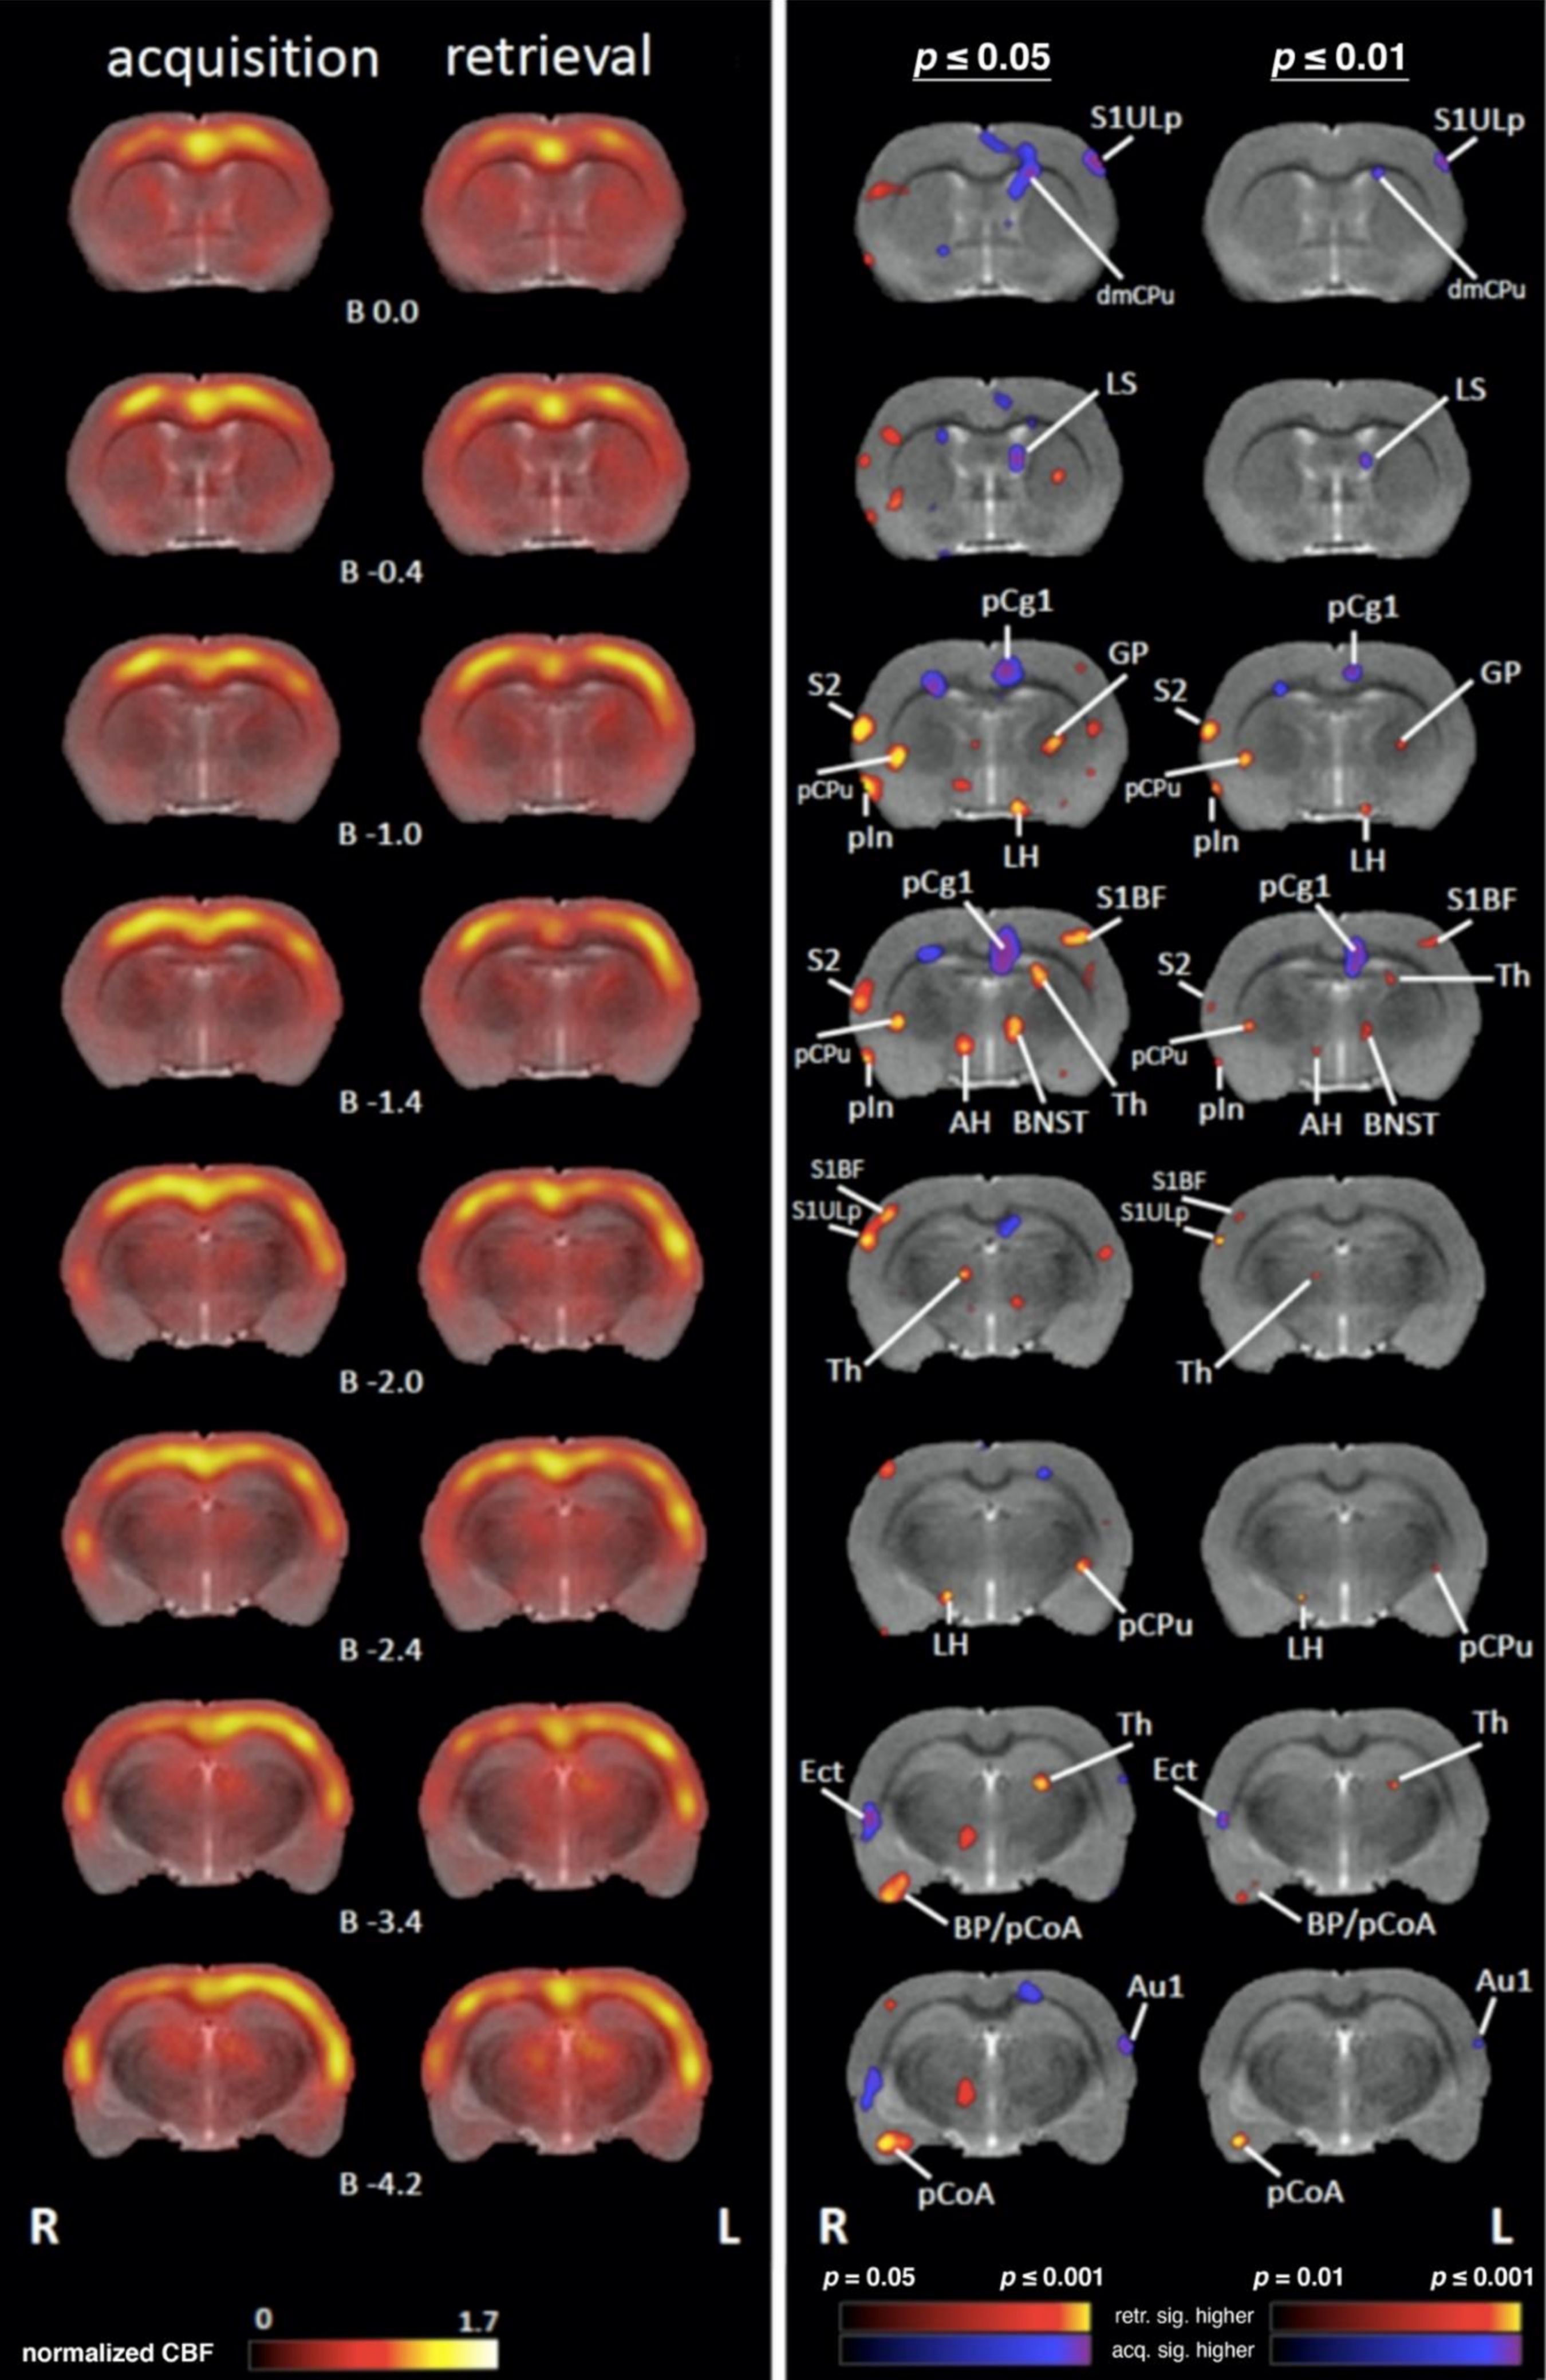

4.1. Comparing Regional Cerebral Blood Flow during Acquisition and Retrieval

4.1.1. Sensory/Motor Cortex

4.1.2. Subcortical Systems

4.1.3. Association and Prefrontal Cortices

4.1.4. Medial Temporal Lobe (MTL)/Limbic Regions

4.1.5. Limbic Output Regions